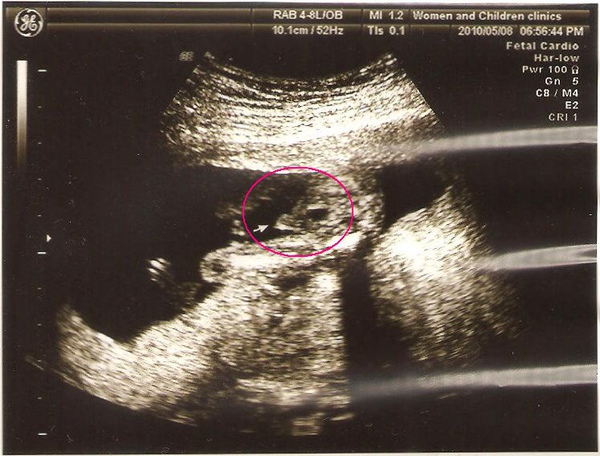

然後又跟我說一次:男生喔~你看,確認了!上次就跟你說了吧~

拍到就好,還特地用箭頭指出來...